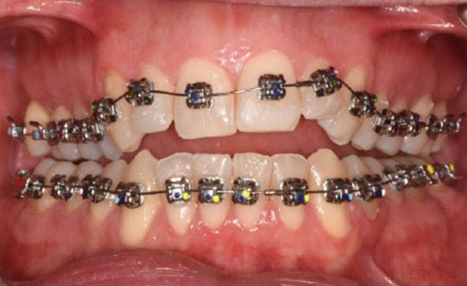

From the outset, bracket placement was the cornerstone of the treatment strategy. The upper central incisors were bonded 1–1.5 mm more gingivally than the canines, with laterals slightly lower, to recreate a natural curvature and protect the smile arc. Variable torque brackets were selected individually for each anterior tooth, according to its specific requirements. This feature of the Damon Ultima system represents a significant advantage: it combines the low-friction benefits of self-ligation with earlier expression of anterior torque. When paired with the rapid arch development characteristic of the system, this approach allows for the ideal torque to be achieved very early in treatment. As a result, proclination of the incisors is effectively avoided while maintaining efficient alignment.

The initial alignment was performed with light CuNiTi archwires, promoting gradual expansion and alignment while avoiding heavy forces. Progressively, the treatment advanced to the final 0.018 x 0.0275 stainless steel archwires, ensuring full torque expression and establishing control over the occlusal plane.

Given the patient’s vertical pattern and open bite tendency, posterior bite turbos were incorporated early to control extrusion and stabilize the vertical dimension. As treatment progressed, refinements included rebonding the upper anterior brackets to fine-tune torque and smile arc display. Crossbite elastics were also introduced to correct the transverse discrepancy in a controlled manner.

The final 4 months were focused on arch coordination and detailling.

Individually coordinated stainless steel archwires, using the WALA ridge described by Dr. Andrews as the reference

(image: Finishing wires)